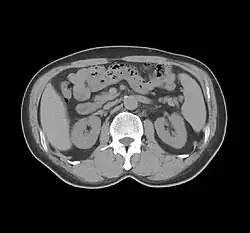

Sir Godfrey Newbold Hounsfield (/ˈhaʊnzfiːld/ HOWNZ-feeld; 28 August 1919 – 12 August 2004)[2][3][4][5][6] was a British electrical engineer who shared the 1979 Nobel Prize for Physiology or Medicine with Allan MacLeod Cormack for his part in developing the diagnostic technique of X-ray computed tomography (CT).[7][8][9][10][11]

His name is immortalised in the Hounsfield scale, a quantitative measure of radiodensity used in evaluating CT scans. The scale is defined in Hounsfield units (symbol HU), running from air at −1000 HU, through water at 0 HU, and up to dense cortical bone at +1000 HU[12][13] and more.

While on an outing in the country, Hounsfield came up with the idea that one could determine what was inside a box by taking X-ray readings at all angles around the object. He then set to work constructing a computer that could take input from X-rays at various angles to create an image of the object in "slices". Applying this idea to the medical field led him to propose what is now known as computed tomography. At the time, Hounsfield was not aware of the work that Cormack had done on the theoretical mathematics for such a device. Hounsfield built a prototype head scanner and tested it first on a preserved human brain, then on a fresh cow brain from a butcher’s shop, and later on himself. On 1 October 1971, CT scanning was introduced into medical practice with a successful scan on a cerebral cyst patient at Atkinson Morley Hospital in Wimbledon, London, United Kingdom.[16] In 1975, Hounsfield built a whole-body scanner. The principles of computed tomography developed by Hounsfield remain in use today (2022).